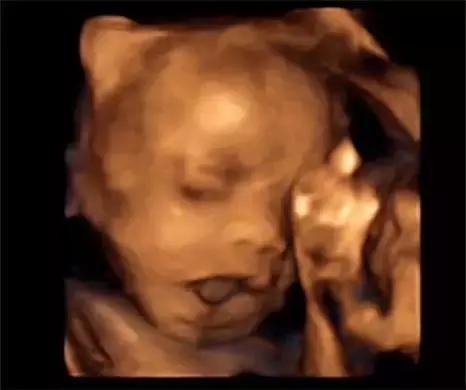

四维彩超可立体显示胎儿的颜面部、各器官的发育情况以及胎儿的年龄、大小等,甚至胎儿在母体里的状态,动作也可以观察到;对胎儿畸形,如唇裂、腭裂、脊柱裂、骨骼发育异常、心脏、大脑畸形等能早期诊断。

四维和三维原理一样,三维是静态的,四维是动态的结果,关键是对羊水多少的判断和处理,三维和四维都是一种比较准确的排除胎儿的外观的畸形的检查手段,三维只能拍摄到宝宝的照片,四维可以录制宝宝视频的。 三维彩超侧重观察五脏六腑是否畸形,排除结构畸形。四维彩超还观察运动神经系统是否正常,运动是否协调。